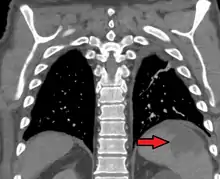

| Splenic infarct seen on CT | |

An abdominal CT scan is the most commonly used modality to confirm the diagnosis,[3] although abdominal ultrasound can also contribute.[5][6][7]